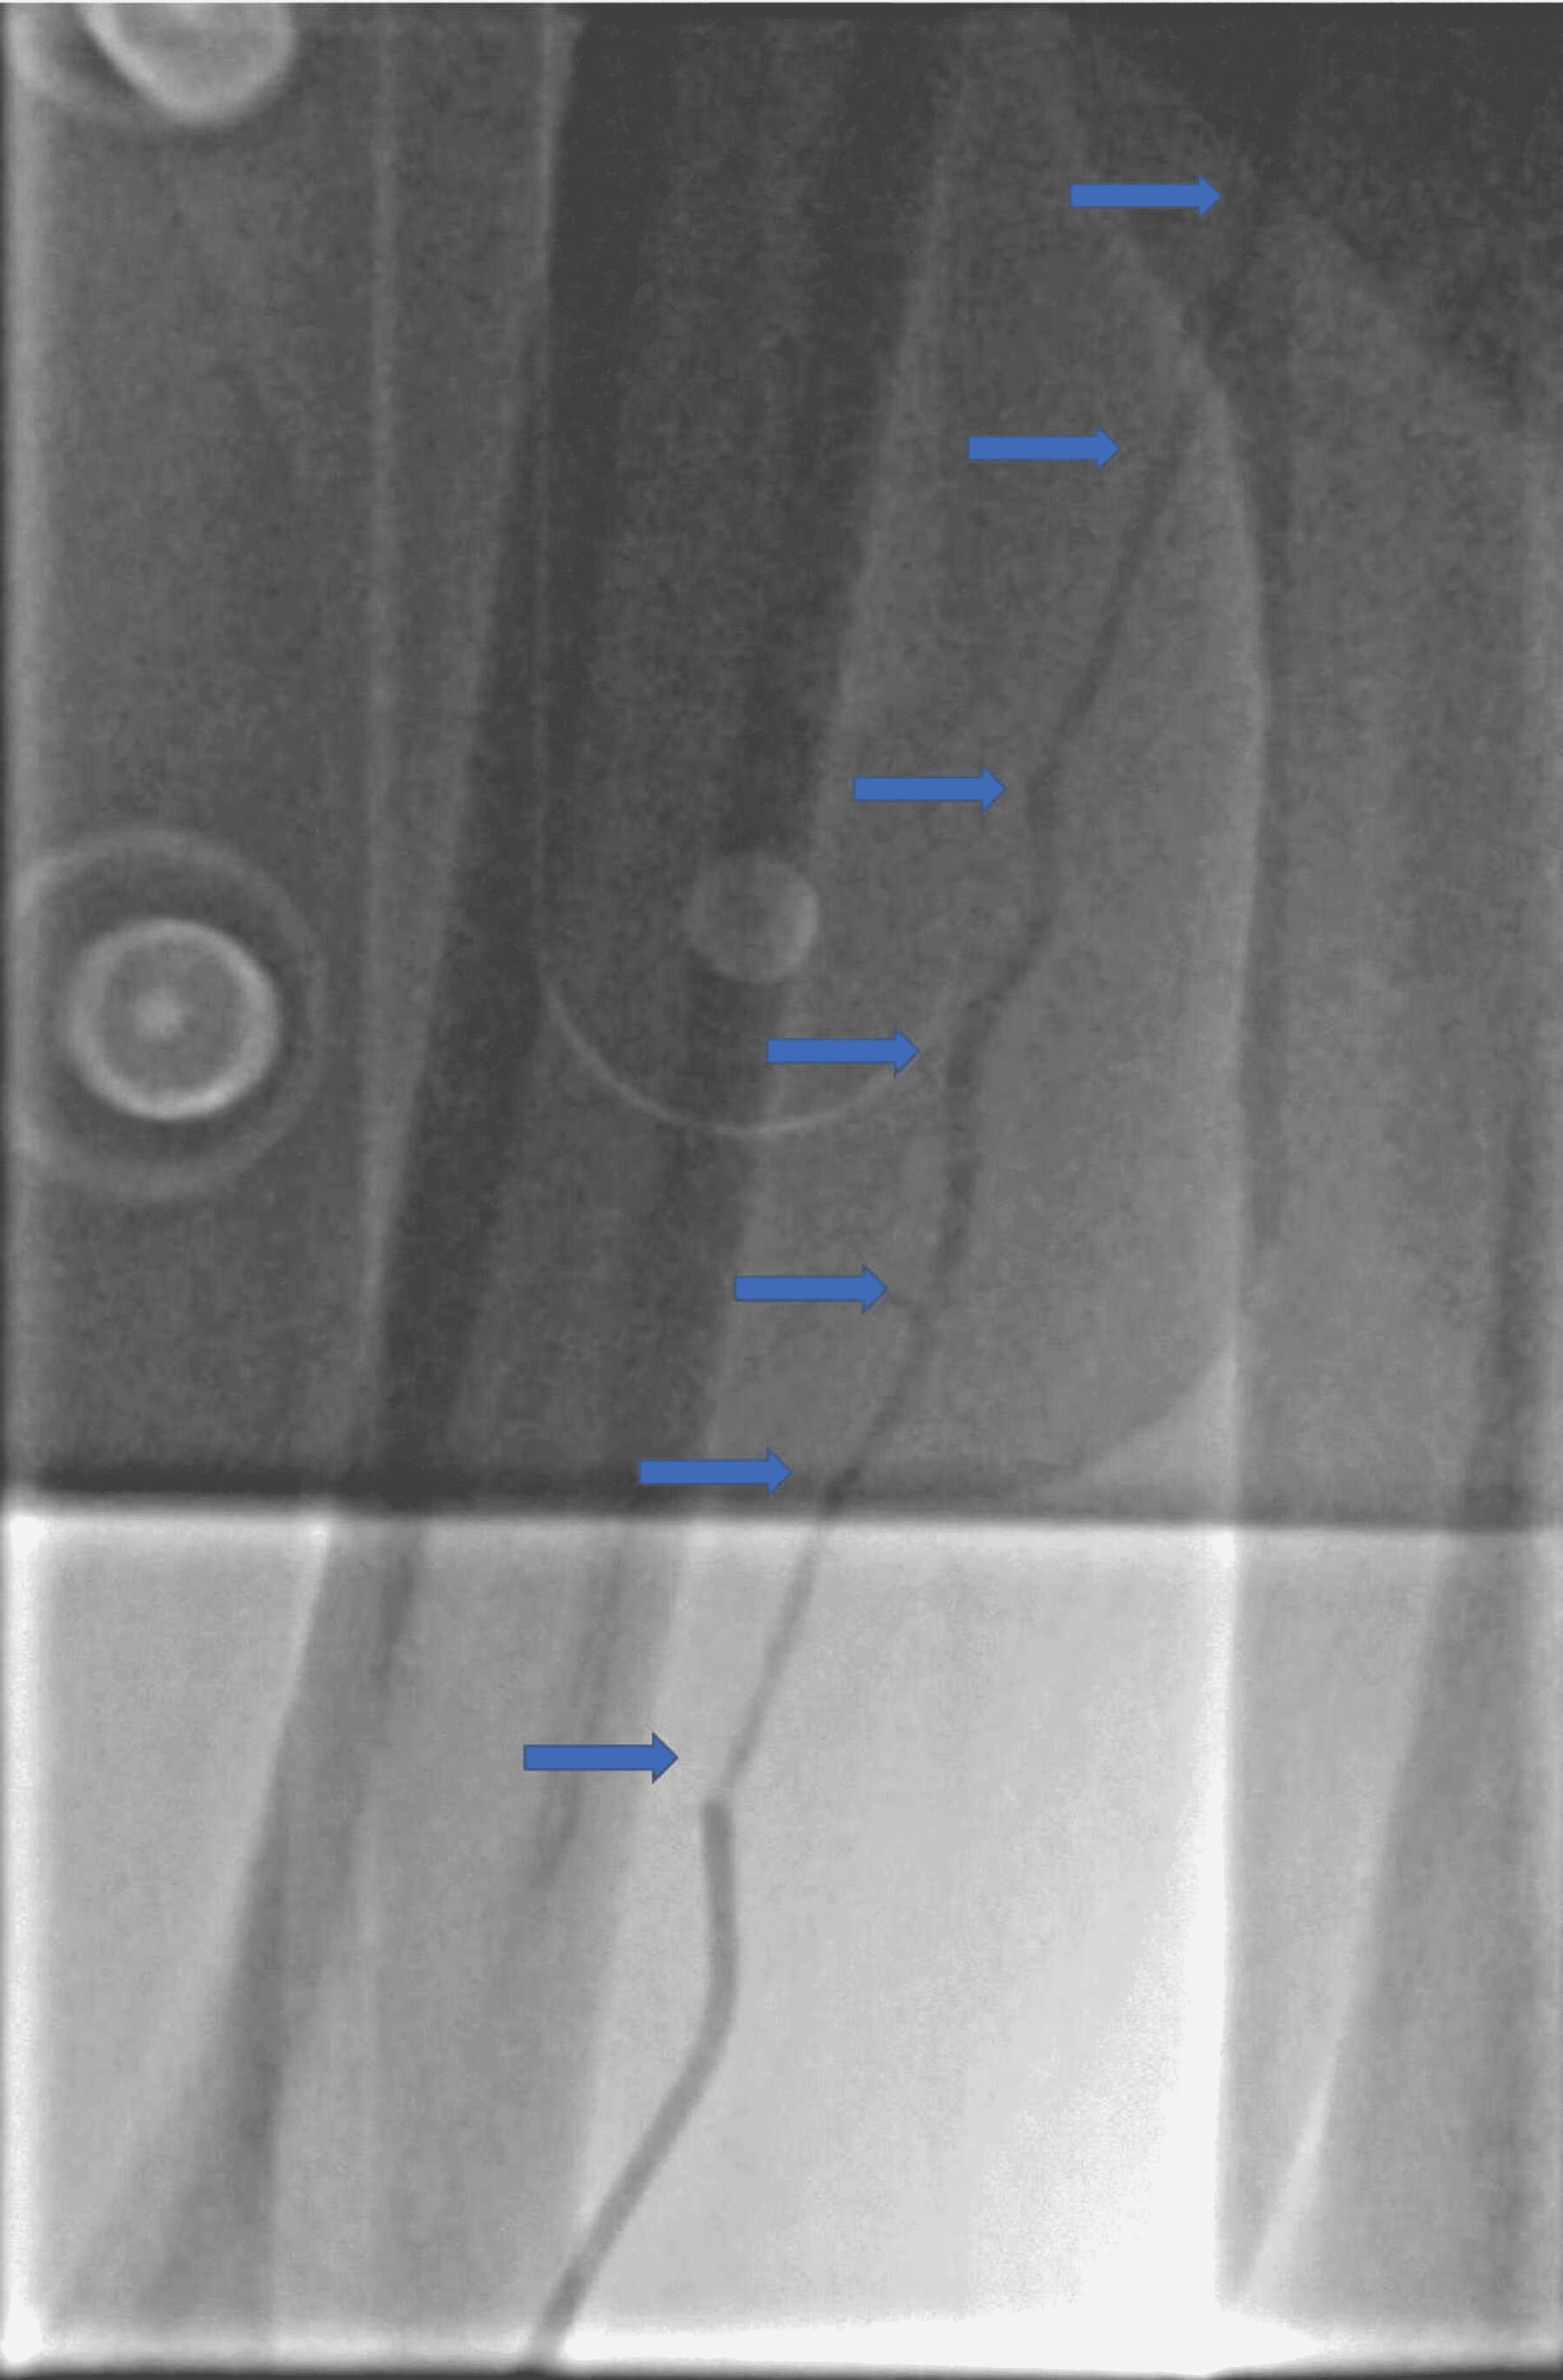

Antegrade venography depicting spasm of the popliteal vein (short Spasm With Catheter When inserted, catheters can sometimes cause bladder irritation, leading to bladder spasms. Bladder spasms may occur because the catheter is unstable inside the bladder, as a result of a neurogenic bladder, an irritable. These flexible tubes, used to drain urine from the bladder, commonly cause bladder spasms. Ureteral stents (tubes to help drain the kidney and. Urinary tract infections and. Spasm With Catheter.

CatheterInduced Venous Spasm Circulation Spasm With Catheter Bladder spasms can also be symptoms of neurogenic bladder. Inserting a catheter can irritate your bladder, causing spontaneous, painful spasms. Ureteral stents (tubes to help drain the kidney and. Bladder spasms happen when your bladder muscles tighten or contract. Bladder spasms can be painful and often lead to an urge to urinate. These flexible tubes, used to drain urine from. Spasm With Catheter.

CatheterInduced Venous Spasm Circulation Spasm With Catheter These flexible tubes, used to drain urine from the bladder, commonly cause bladder spasms. Bladder spasms happen when your bladder muscles tighten or contract. Medical conditions such as neurogenic bladder, multiple sclerosis,. Incontinence may occur if the bladder spasms continue because the. This may give you the urge to urinate more often. Inserting a catheter can irritate your bladder, causing. Spasm With Catheter.

(PDF) CatheterInduced Venous Spasm Spasm With Catheter Incontinence may occur if the bladder spasms continue because the. Bladder spasms may occur because the catheter is unstable inside the bladder, as a result of a neurogenic bladder, an irritable. Ureteral stents (tubes to help drain the kidney and. Medical conditions such as neurogenic bladder, multiple sclerosis,. When inserted, catheters can sometimes cause bladder irritation, leading to bladder spasms.. Spasm With Catheter.

CatheterInduced Venous Spasm Circulation Spasm With Catheter Inserting a catheter can irritate your bladder, causing spontaneous, painful spasms. Urinary tract infections and irritation from using a catheter are also common culprits. Bladder spasms happen when your bladder muscles tighten or contract. Bladder spasms may occur because the catheter is unstable inside the bladder, as a result of a neurogenic bladder, an irritable. Bladder spasms can be painful. Spasm With Catheter.